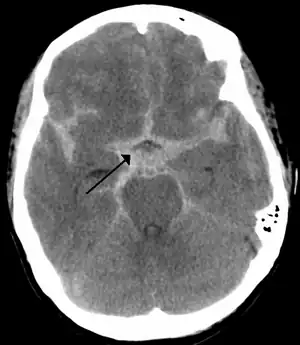

Subarachnoid bleed

CT scan of the brain showing subarachnoid hemorrhage as a white area in the center and stretching into the sulci to either side (marked by the arrow)

If an aneurysm ruptures, blood leaks into the space around the brain. This is called a subarachnoid hemorrhage. Onset is usually sudden without prodrome, classically presenting as a "thunderclap headache" worse than previous headaches.[6][7] Symptoms of a subarachnoid hemorrhage differ depending on the site and size of the aneurysm.[7] Symptoms of a ruptured aneurysm can include: